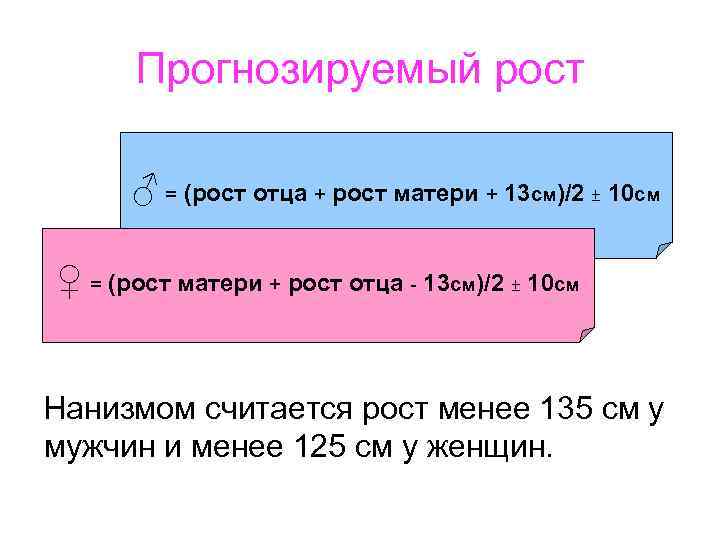

Прогнозируемый рост ♂ = (рост отца + рост матери + 13 см)/2 ± 10 см ♀ = (рост матери + рост отца 13 см)/2 ± 10 см Нанизмом считается рост менее 135 см у мужчин и менее 125 см у женщин.

Прогнозируемый рост ♂ = (рост отца + рост матери + 13 см)/2 ± 10 см ♀ = (рост матери + рост отца 13 см)/2 ± 10 см Нанизмом считается рост менее 135 см у мужчин и менее 125 см у женщин.